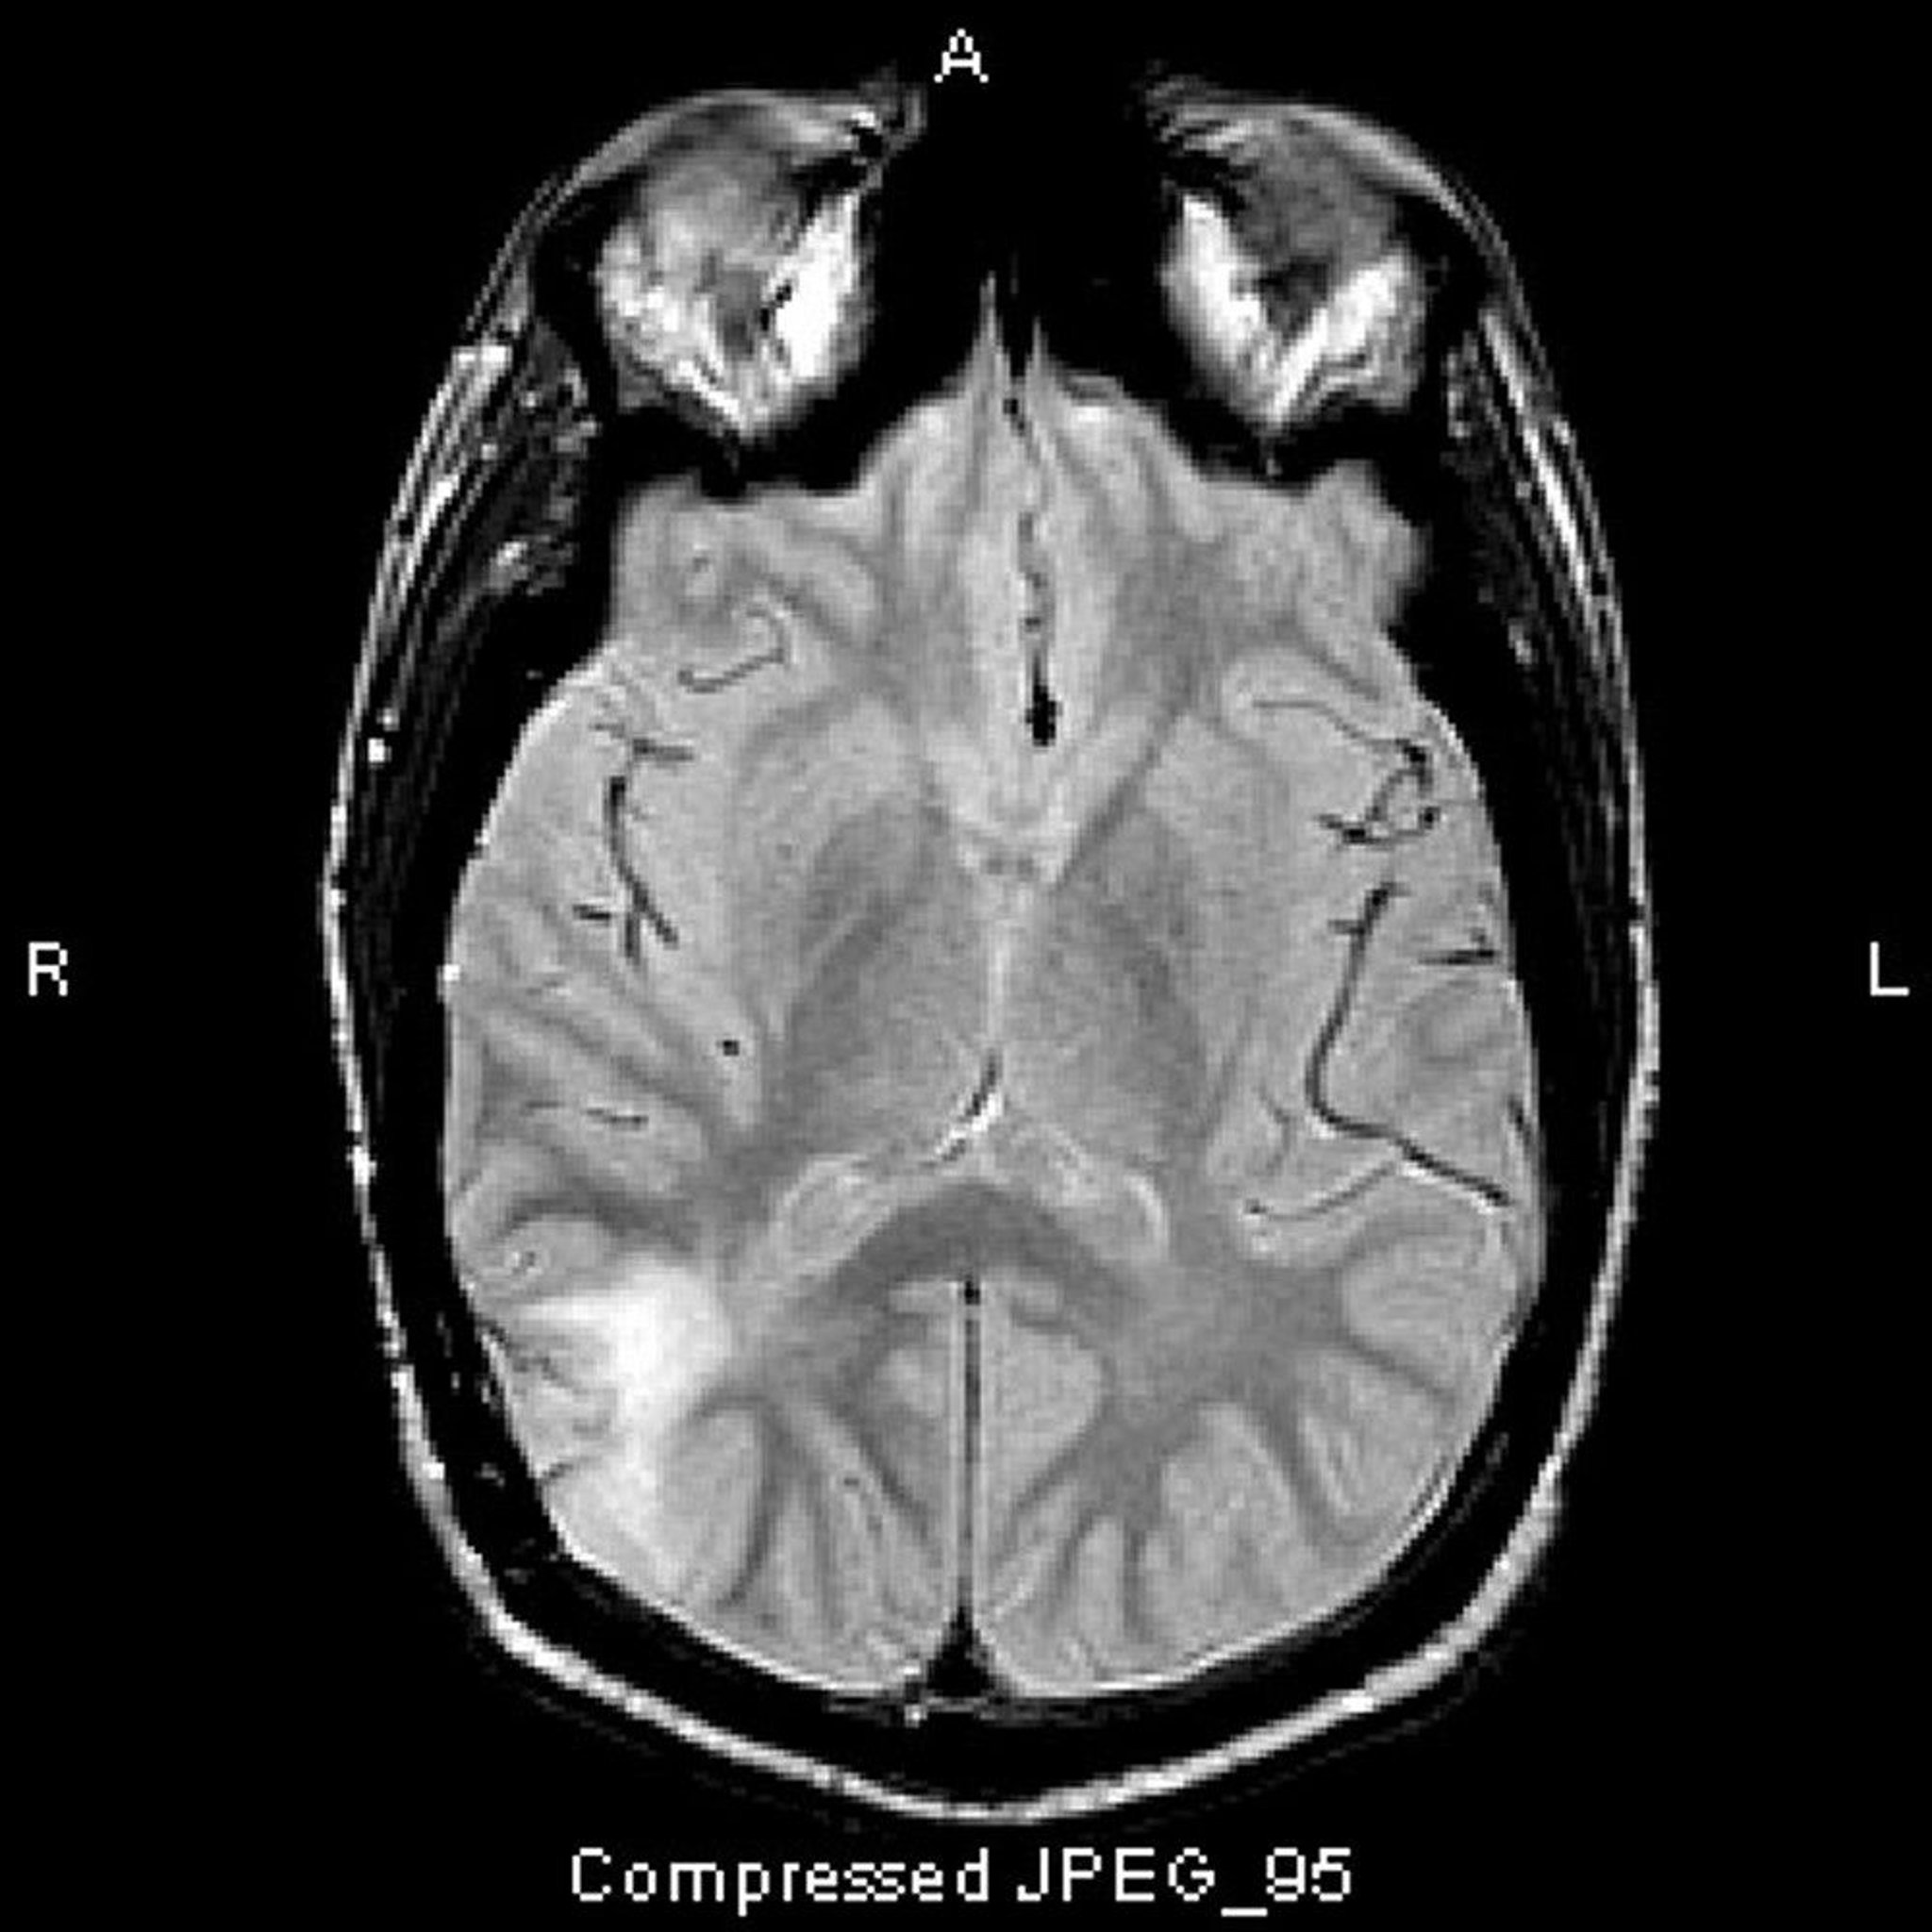

Anaplastic Astrocytoma

This T2-FLAIR MRI scan shows a white signal in the posterior temporal lobe. The signal is not enhanced by contrast. It is an anaplastic (grade III) astrocytoma.

Image courtesy of William R. Shapiro, MD.